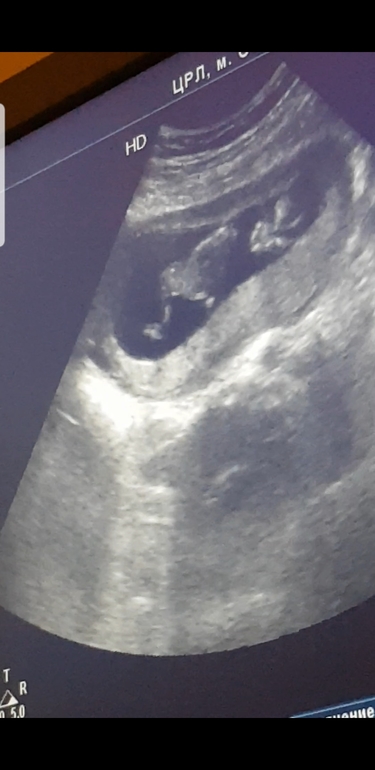

Elena в Благополучная беременность 7 лет 12 полных недель узи. УЗИ, КТГ, доплер На кого похоже? Может кто разбирается?или есть ваши фото узи на этом сроке.. Посмотрите еще 20 записей на эту тему Отменить Ответить Анастасия Вы че, прикалываетесь) Тут кроме матки ничего не видно 17.03.2019 Ответить Agita Плохо видно, но по-моему девочка) 15.03.2019 Ответить 1 скрининг пройден!) Первый скрининг -платно или нет? Чаты Беременных Выберите чат: Январята-2026 Февралята-2026 Мартята-2026 Апрелята-2026 Майчата-2026 Июнята-2026 Июлята-2026 Августята-2026